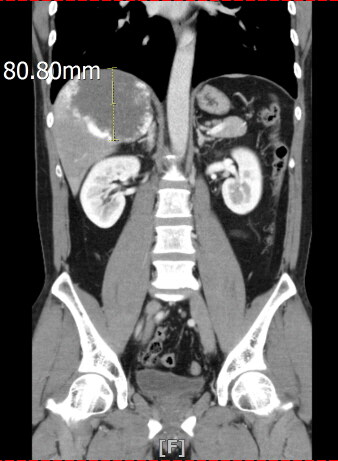

낼 병원 가는데 의사선생님 사무실 위치가 이상하다..... Anonymous | 2025.09.25 17:22 | 조회 12 https://qquing.net/bbs/board.php?bo_table=humor&wr_id=1642115 주소 복사 이전글 다음글 랜덤 만화 목록 본문 내 상태....... 암 아님....... 추천 0 비추천 0